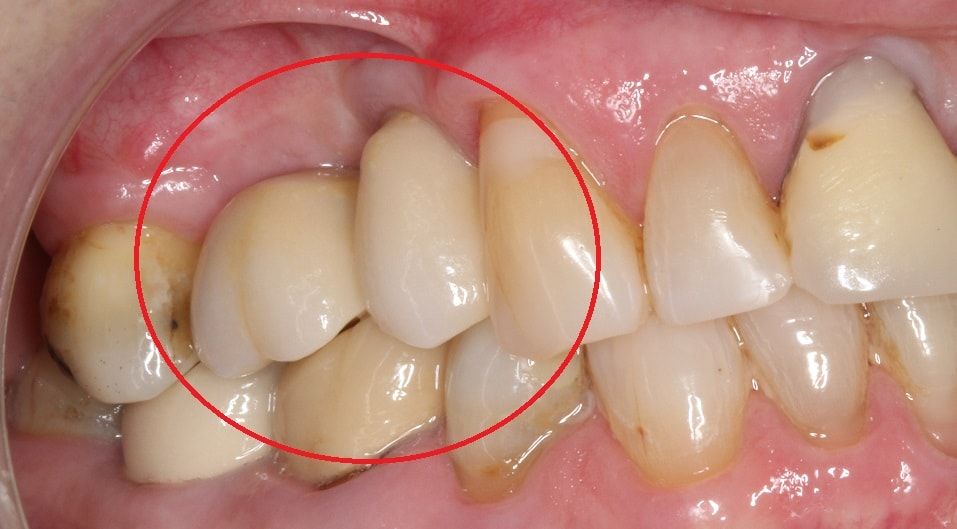

Протезирование - установка коронки на имплантат

Финальный этап восстановления зубного ряда, крепление коронковой части зуба к вросшему в костную ткань титановому основанию - имплантату.

При протезировании на имплантатах модель челюсти и конкретного зуба, и моста и всей челюсти строится в программах 3D проектирования. Они позволяют точно рассчитать высоту и ширину коронки и длину абатмента, основания соединяющего коронку с имплантом.

Коронки и абатменты изготавливаются индивидуально, по 3D модели челюсти пациента.

3D моделирование и точность фрезерного оборудования позволяет создавать конструкции которые сразу идеально устанавливаются и не меняют привычный прикус пациента, что нередко происходит при установке металлокерамических коронок изготовленных методом литья.